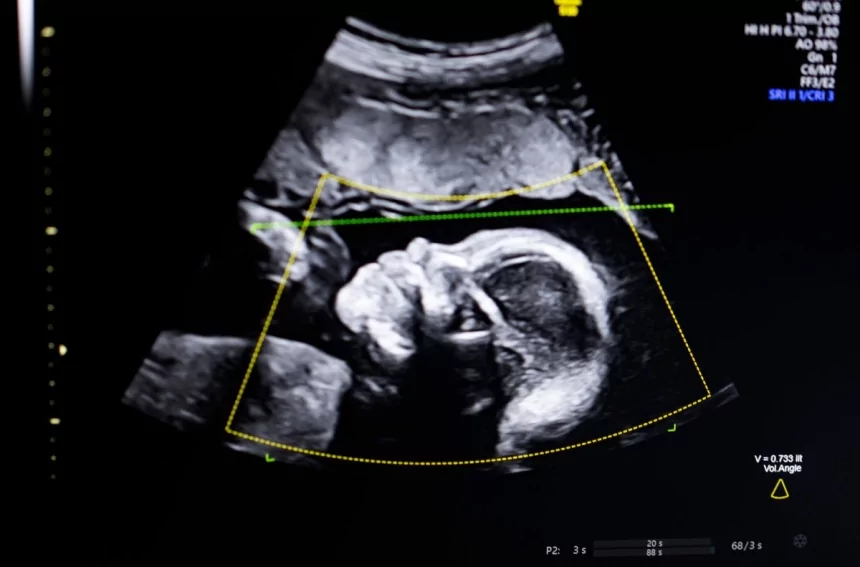

TechCrunch Disrupt Battlefield 2023 winner, Biotics AI, announced on Monday that it has received FDA clearance for its AI software that helps detect fetal abnormalities in ultrasound images.